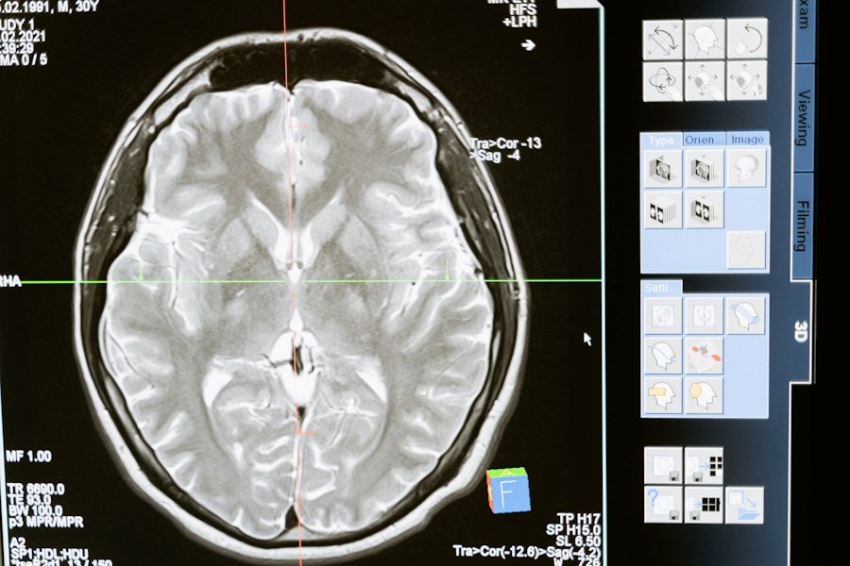

Нейрофизиологи University of Southern California (USC) сделали прорывное открытие: они доказали, что формирование новых нейронов в мозге — процесс, известный как нейрогенез — играет ключевую роль в сохранении вербальной памяти и воспоминаний о диалогах. Это открытие поможет в разработке методов лечения когнитивных расстройств, связанных с эпилепсией, сообщает сайт USC.

Исследование проводилось с участием 40 добровольцев, страдающих мезиальной височной эпилепсией — одной из самых распространённых форм заболевания. Ученые наблюдали за их когнитивными функциями на разных стадиях болезни и изучали образцы ткани гиппокампа, изъятые во время хирургических операций по удалению очагов эпилепсии.

Гиппокамп, отвечающий за формирование воспоминаний, является единственным отделом мозга, где нейрогенез продолжается на протяжении всей жизни. Учёные обнаружили, что припадки эпилепсии постепенно замедляют этот процесс, что объясняет резкое ухудшение памяти и ясности ума через 20 лет после постановки диагноза.